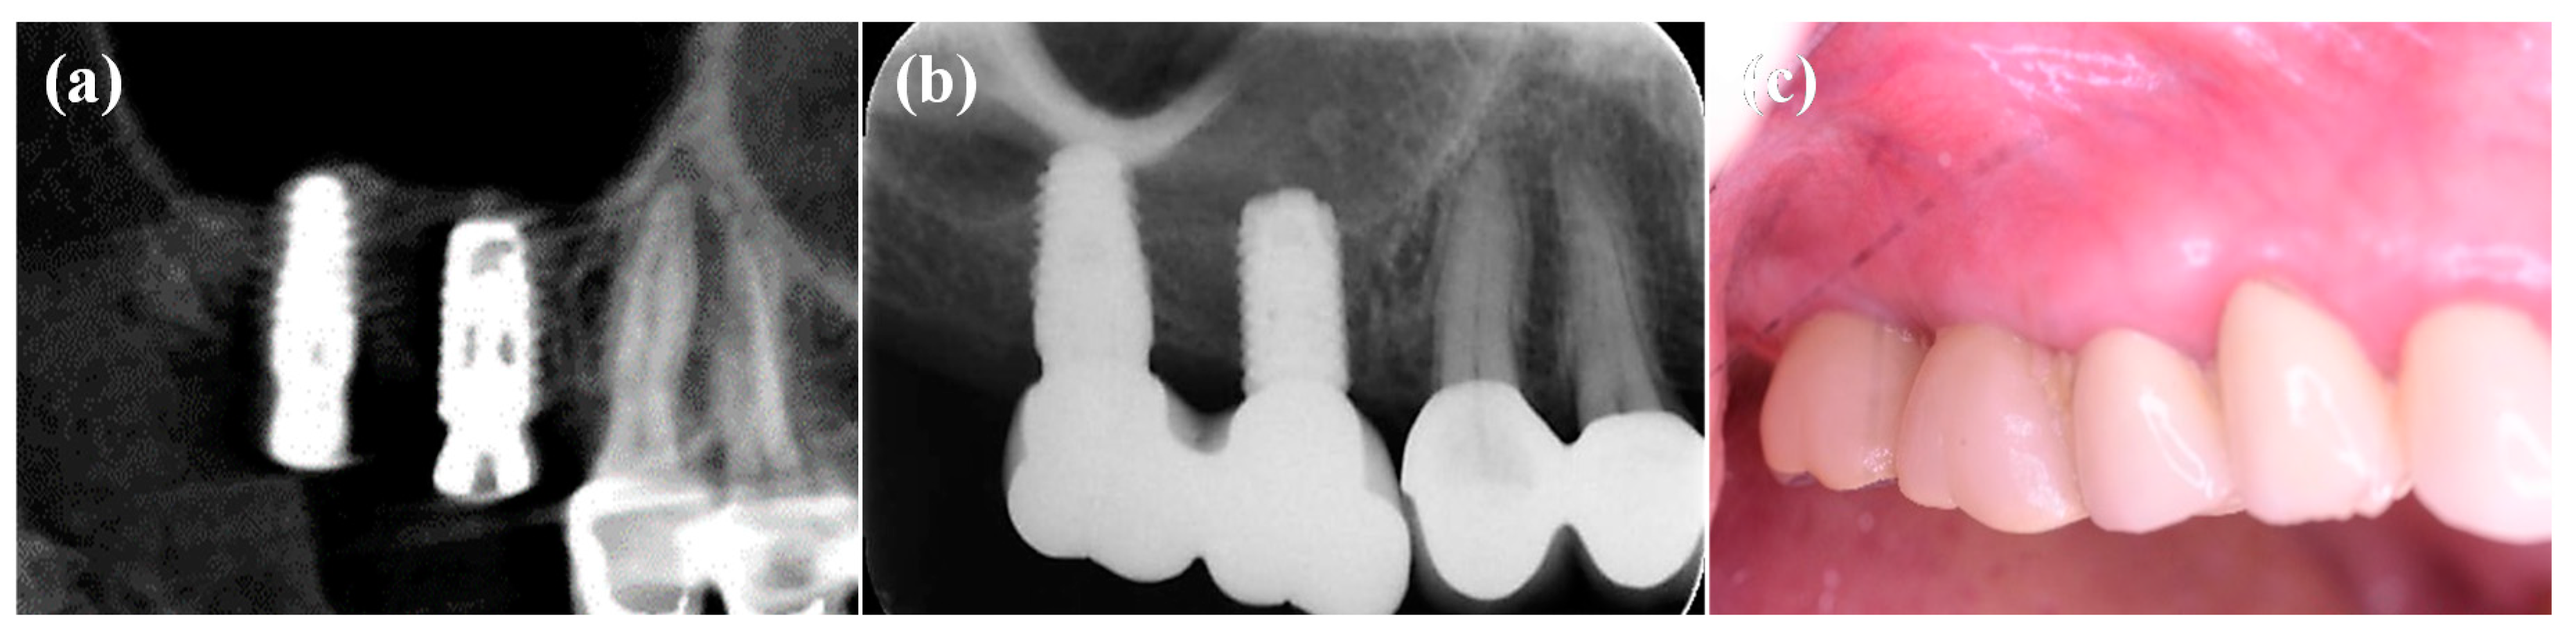

3.4. Clinical Evaluations of the IDCT-Modified Ti Implant